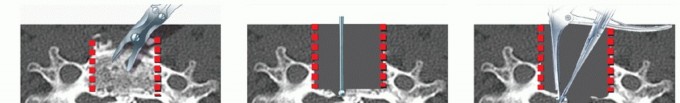

### TECH FIG 1 • Limits of corpectomy. A. The width of the corpectomy is based on that necessary to decompress the spinal cord and can be estimated on preoperative imaging. B. In general, a corpectomy spanning from the medial border of one uncinate to the other will be sufficient at the vertebral body level. (continued) The width of the corpectomy required to decompress the cord should be based on preoperative imaging studies (TECH FIG 1). Generally, sufficient decompression will occur if the width of the decompression spans from uncinate to uncinate. Wider decompressions beyond the medial border to the uncinates are typically performed at the disc level, where a combination of cord and root compression may occur, but are not necessary at the vertebral body level, where only the spinal cord is compressed.

TECH FIG 1 • (continued) C. At the level of the disc space, a wider decompression may be necessary for satisfactory root decompression (yellow lines). Staying within the uncinates will allow for thorough decompression while avoiding vertebral artery injury, unless a vertebral artery anomaly exists. Such anomalies are more likely to occur within the vertebral body rather than the disc spaces, and they should be recognized on preoperative imaging to avoid injury. 2. ## Cervical Corpectomy The edges of the corpectomy are longitudinally delineated with a high-speed burr from uncinate to uncinate to define the safe limits of the decompression. Next, a Leksell rongeur can be used to quickly remove large fragments of vertebral body bone (TECH FIG 2). This bone should be saved for grafting. Once the cancellous bone is removed grossly, fine decompression then proceeds with a high-speed burr. Under direct visualization, a high-speed burr is used to remove bone until a thin shell of posterior cortex remains. Microcurettes and Kerrisons are then used to flake off the remaining bone.